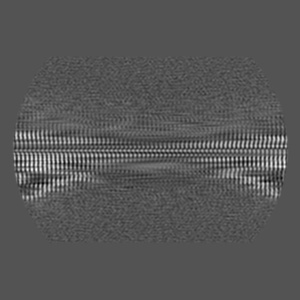

CTE typeIII tau filament from Guam ALS/PDC

Helical reconstruction3.4 Å

Tau filaments from amyotrophic lateral sclerosis/parkinsonism-dementia complex adopt the CTE fold.